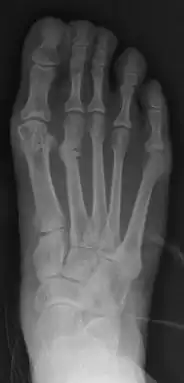

- For severe bunion deformity correction (Fig. 7)

For recurrence correction after fusion procedure (Fig. 9) Metatarsus primus varus deformity and pain recurred 6 months after modified Lapidus procedure and it could also be again corrected by the syndesmosis procedure.